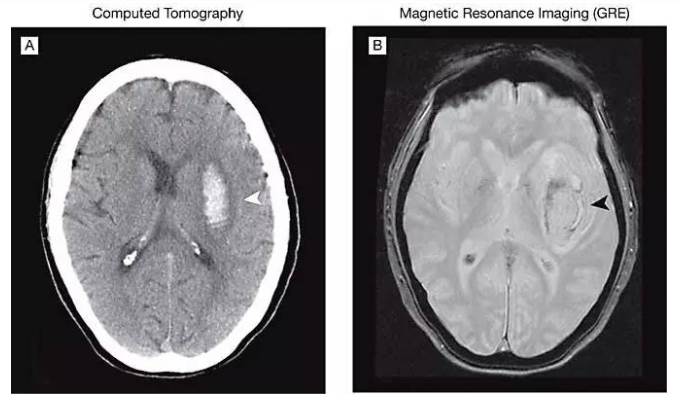

CT 检查主要用于判断人体骨骼的结构和损伤情况,尤其对于出血以及含气体的组织,具有很高的分辨度。除此外,它对人体骨、肺等器官成像也比较好,比如骨折、急性脑出血、骨源性肿瘤以及肿瘤钙化。在胸部扫描中,其对胸腔、肺、心腔中的肿块、出血等很容易检查出来。

MRI检查有较高的软组织分辨率,因而对软组织疾病、中枢神经系统疾病以及头、颈椎、胸椎、腰椎及四肢部位的检查上有很大的优势,所以临床医生对头颅和神经系统疾病,多选用MRI进行检查。

CT扫描可提供骨骼结构良好的细节,最好的一点是CT扫描可同时获得软组织、骨骼和血管的诊断性影像,还能提供令人印象深刻的软组织影像的细节,特别是当应用静脉内造影剂时由于CT扫描速度快,其提供的影像分辨率较高,并且运动伪影较少。

与CT扫描相比,MRI扫描通常提供的细节较少,但能提供更多的软组织细节。当需要分辨不同类型软组织之间细微的差别时,通常会申请MRI检查。